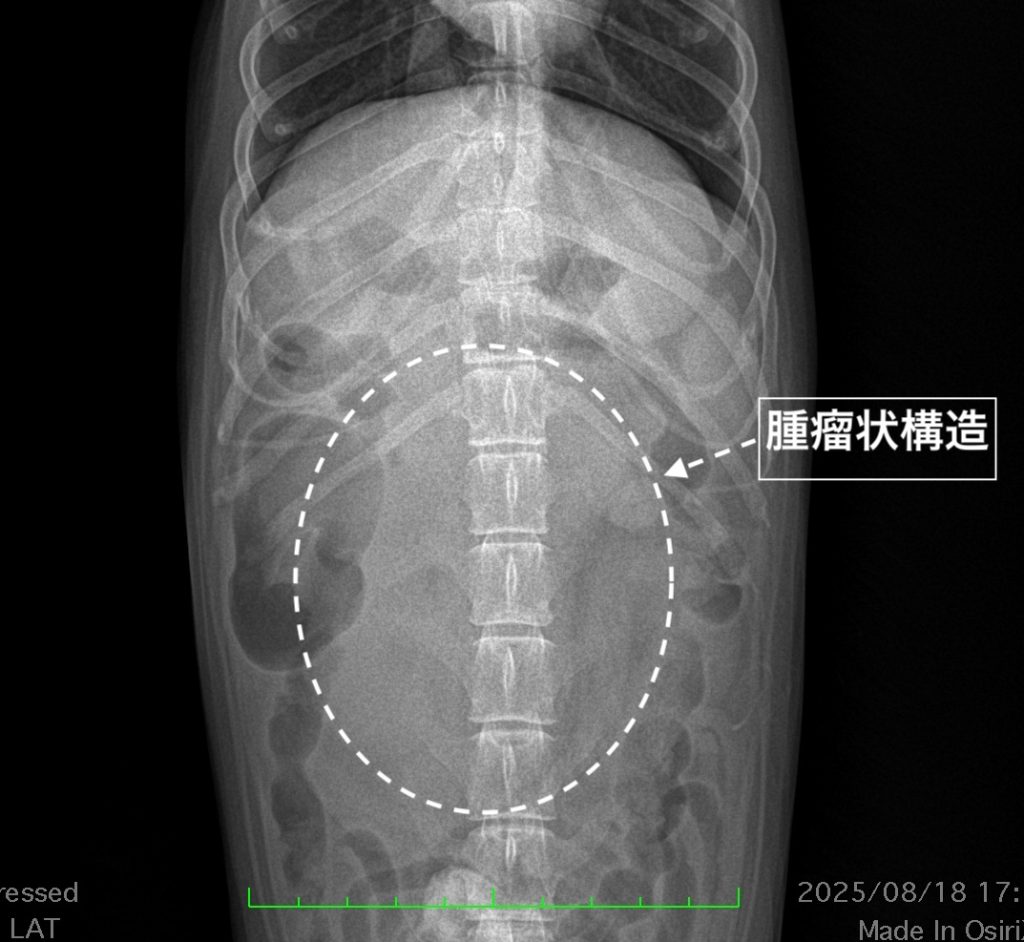

レントゲン検査

上腹部腹腔内正中に腫瘤状構造が認められました。

実際のレントゲン画像です。腹腔内正中に充実性の腫瘤上構造が確認できます。